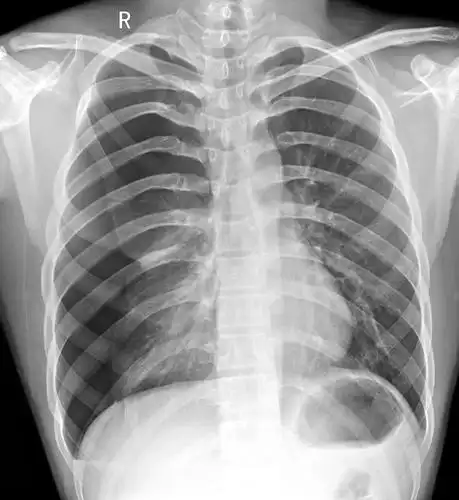

气胸的x线表现,6个病例搞定!

气胸患者胸部x线表现

一侧气胸肺严重压缩

左侧气胸(肺被压缩约20%)